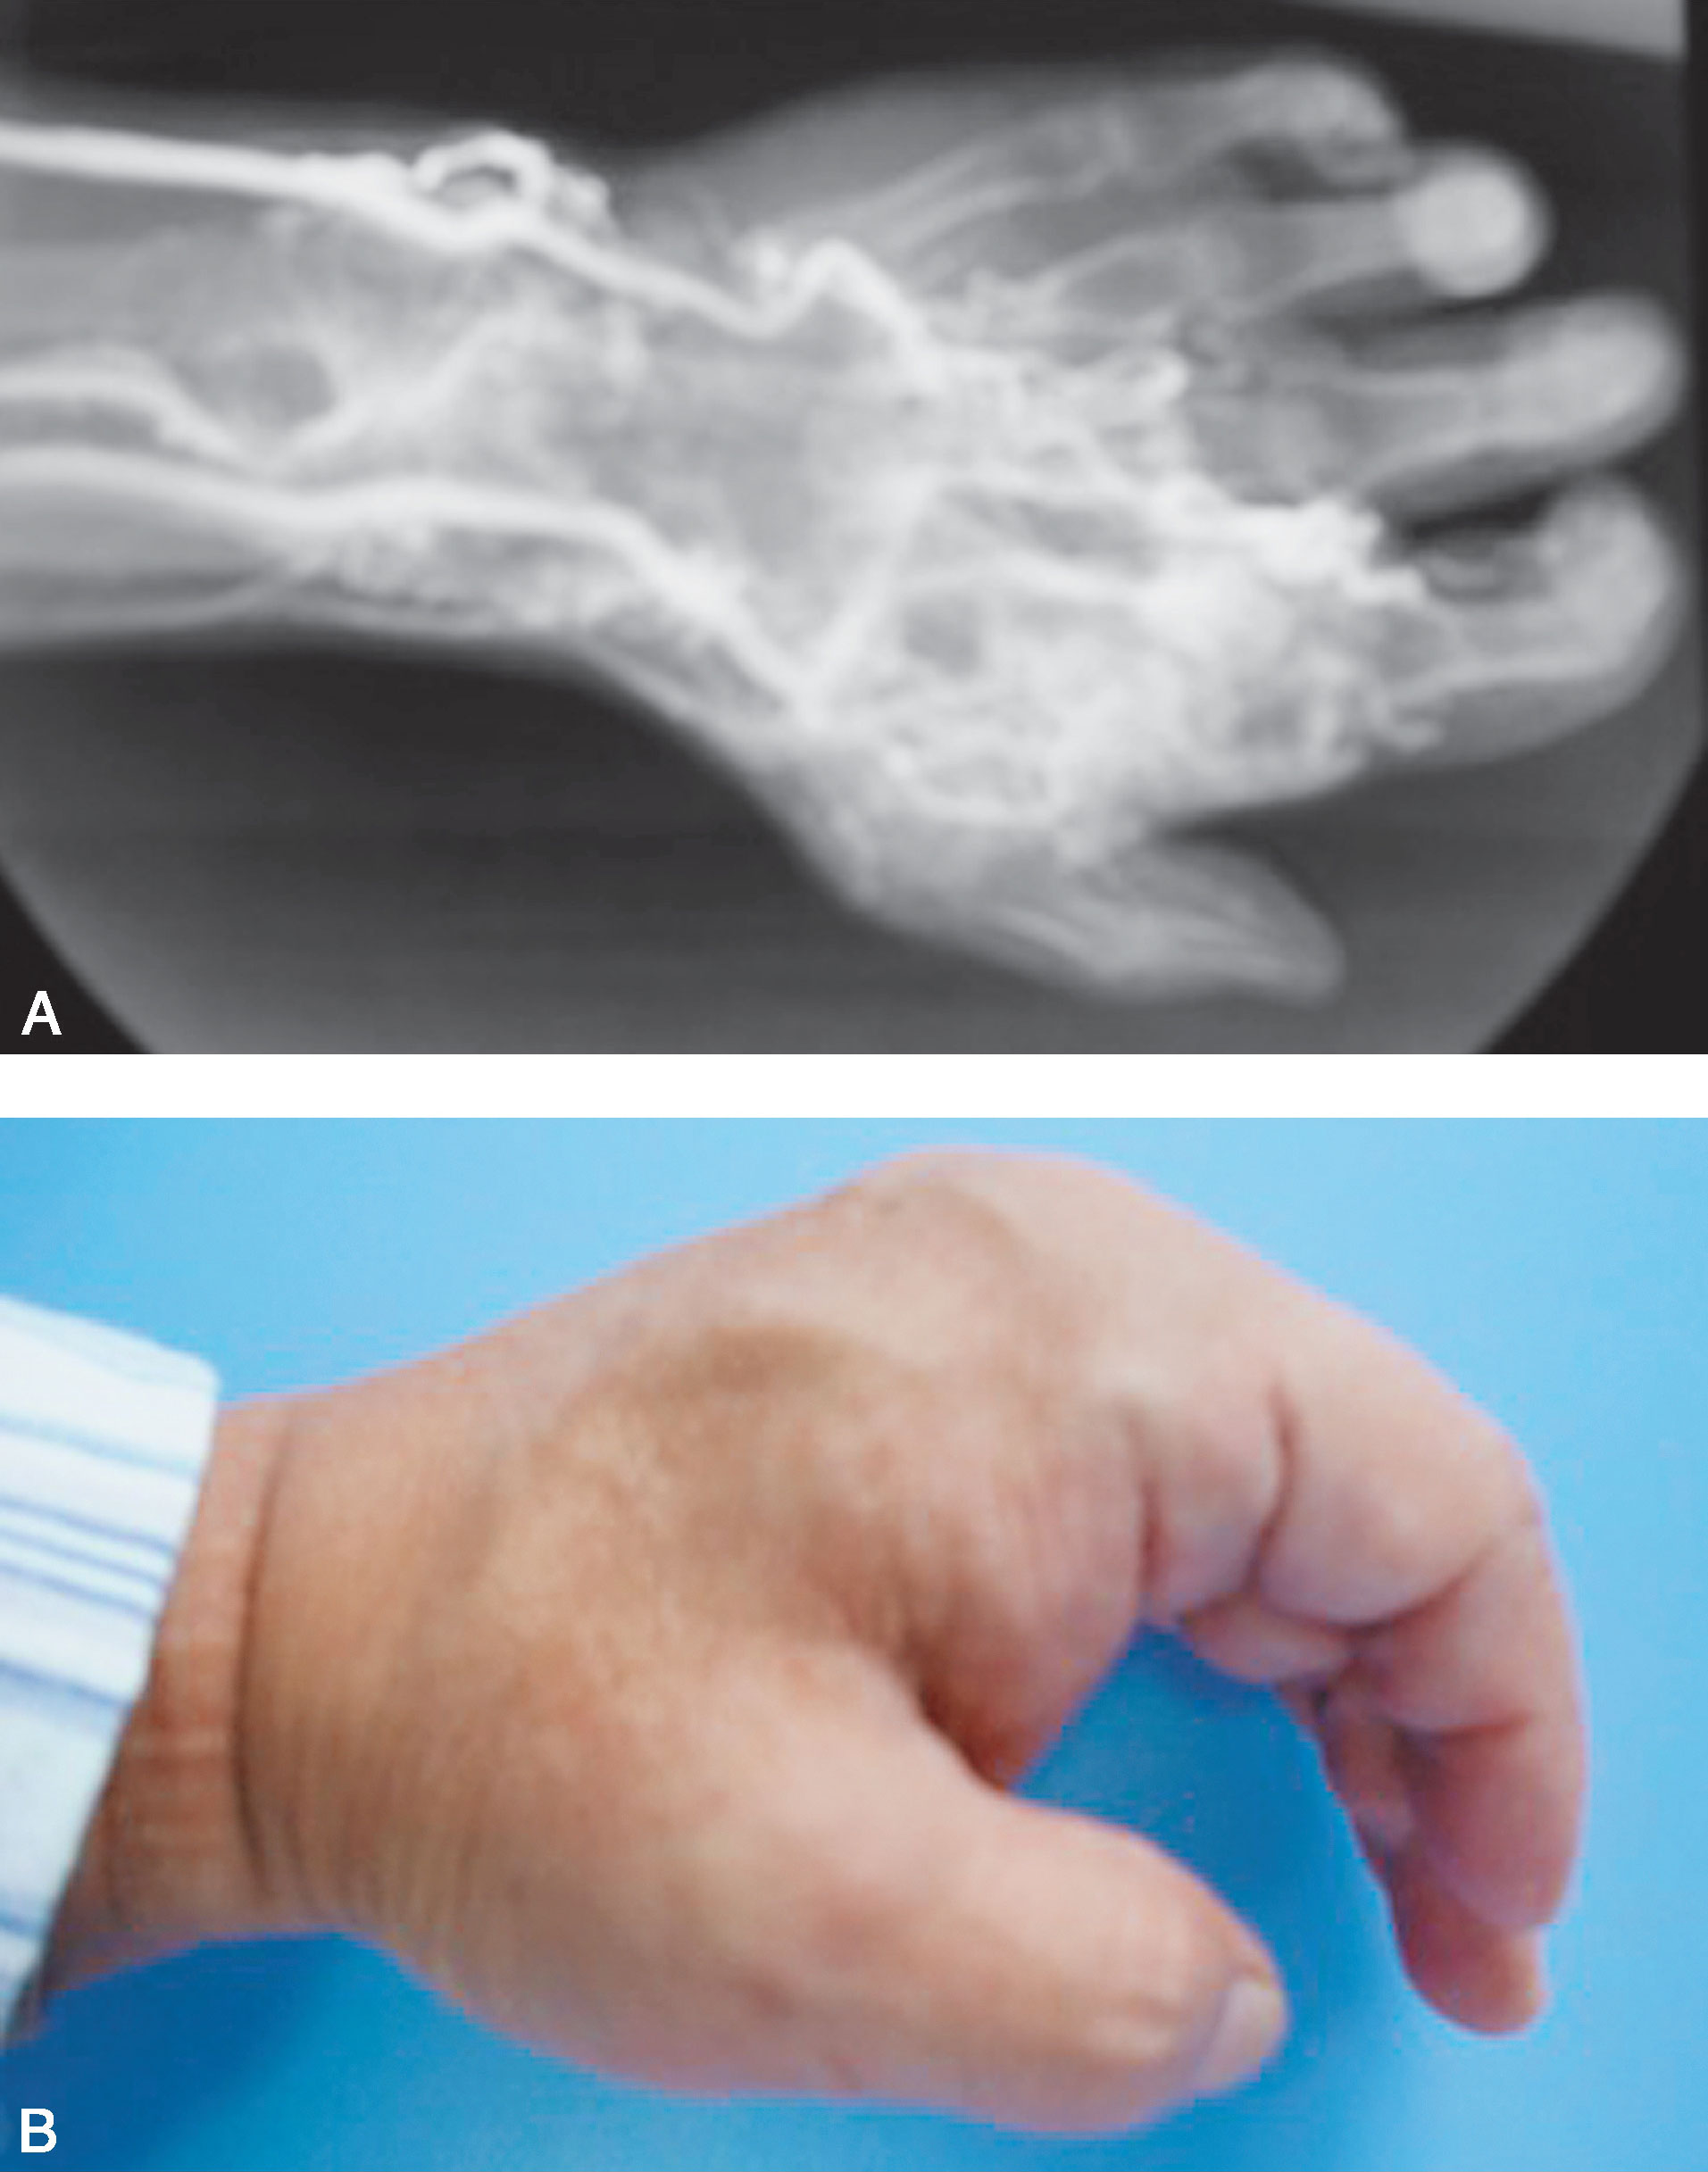

图1-2-31 海绵状血管瘤病例

A.手体位像显示右手拇指蹼内有界限不清的肿物;B.X线片显示右手拇指蹼内海绵状血管瘤、散在的静脉石

图1-2-32 海绵状血管瘤血管造影

血管造影显示拇指蹼内血管瘤

(2)海绵状血管瘤(图1-2-31、图1-2-32)。